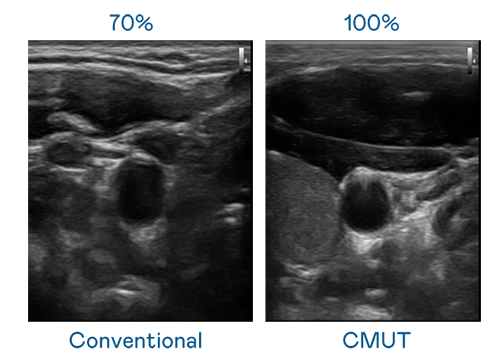

CMUT 技术是一种用电容式微机电元件来产生超音波讯号的技术。与传统 PZT 压电式技术相比,CMUT 频宽增加 30%,更宽频的超音波讯号让影像解析度大幅提升,是实现高影像品质医疗超音波扫描、促进精准医疗发展的关键技术。

大频宽带来超清晰影像

超音波影像的解析度高低,首先取决于探头能发出的讯号频宽。j9国际 CMUT 可提供高清晰的超音波讯号,提供高频宽、高灵敏度、影像纹理细节更高的超音波影像,协助医护人员缩短影像判读时间及利用精准的医疗影像进行诊断。